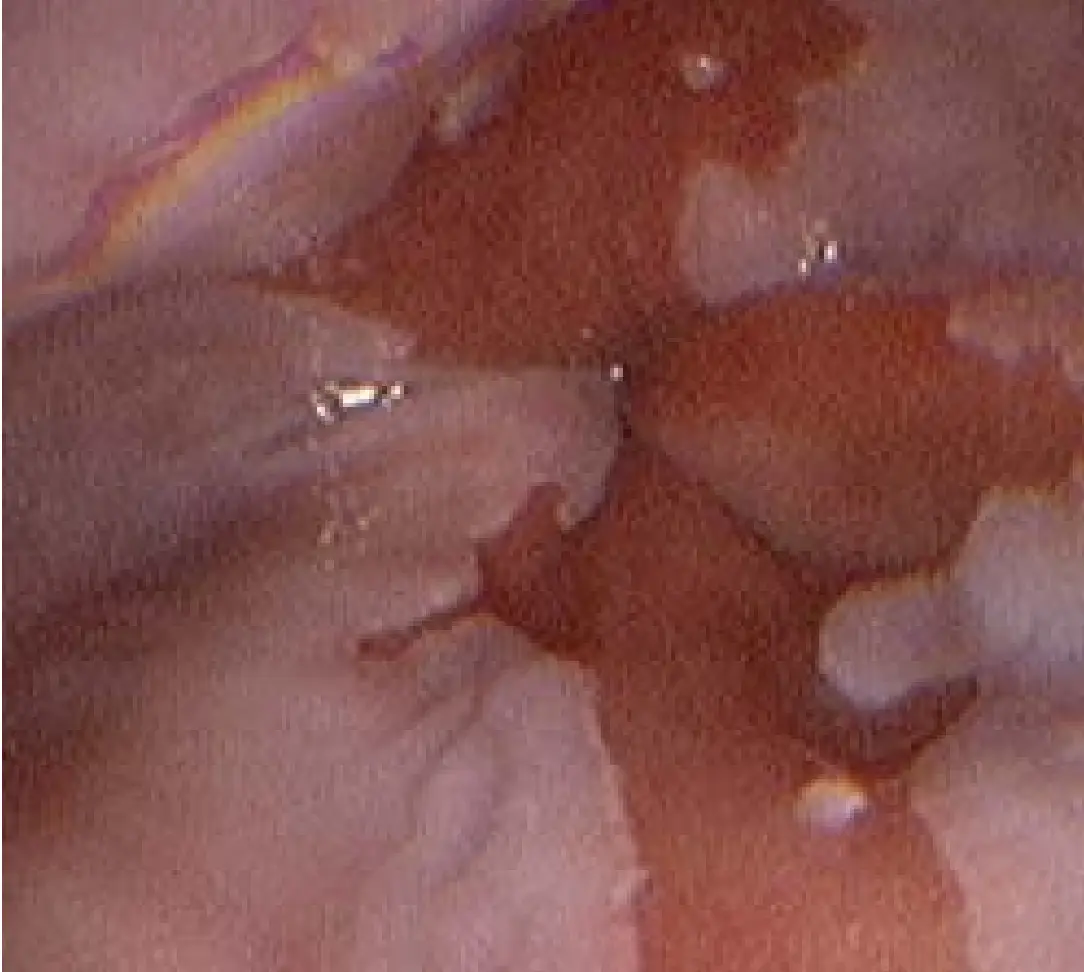

用內視鏡檢視食道下端,可見正常的灰白色鱗狀上皮被鮭紅色的柱狀上皮取代,且延伸超過胃食道交界面(Z-line)向近端,邊緣不規則、片狀分布。此鮭紅色黏膜區塊即為Barrett’s esophagus的典型視覺表徵,代表特殊腸化生(specialized intestinal metaplasia)。